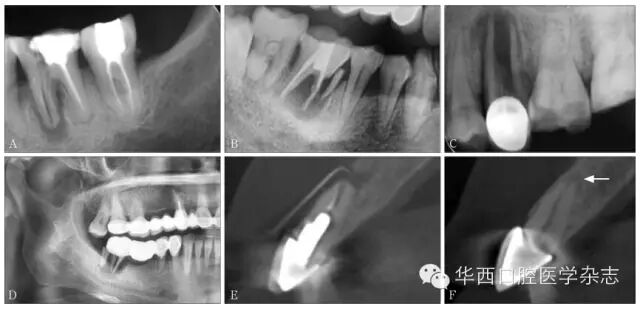

牙根折裂早期仅见根尖孔扩大、根管内径的部分扩大,折线常沿牙根长轴向冠方纵行。随着病变发展,折片分离,多向远端移位,常伴根周及根分叉牙槽骨吸收;也可见斜折或横折,横折者多伴发牙槽骨重度吸收,可见于前磨牙或前牙。根管治疗后的牙根折裂线可表现为充填牙胶的侧方出现缝隙,继而出现根管内径增宽。底穿、侧穿以及桩钉路径偏移引起的折裂常沿病变走行;长烤瓷桥的受力不均也可发生牙根折裂[3](图6)。

AB3646牙根管治疗后折裂;CD25牙冠修复、47烤瓷桥修复后牙根折裂;E11牙桩冠修复后折裂,根尖孔扩大,根尖周骨质吸收;F21同名牙正常牙根,注意二者根尖孔形态的差异(箭头示)。

6 治疗后牙根折裂